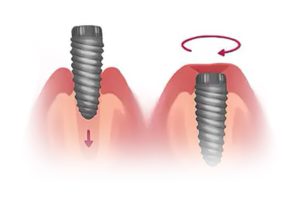

Dental implants come in many shapes and sizes but they can typically be broken down into three main parts; the crown, titanium abutment and the implant fixture. When these three parts are combined, they form the basic structure of a dental implant.

During implant surgery, the fixture of the dental implant will be inserted into the upper and/or lower jaw of the patient, this fixture will act as a replacement of a tooth’s root, bonding with surrounding bone over the course of a few months after the dental implant placement surgery.

1. Implant Placement

The implant fixture is surgically inserted into the jawbone. The fixture acts as a root for the replacement tooth.

2. Osseointegration

The implant fixture is left to recover and fuse to the surrounding jawbone.

3. Affix Abutment

The gum is reopened to expose the implant fixture in order to attach the abutment.

4. Prosthesis Placement

The final prosthesis is permanently cemented to the abutment.